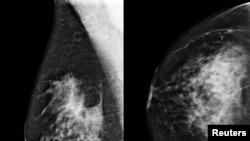

Një studim i bërë së fundmi arrin në përfundimin se mjekët janë në gjendje të zbulojnë kancerin në gji më shpesh në rastet kur përdorin inteligjencën artificiale për të ndihmuar në leximin e rezultateve të mamogramit. Siç njofton korrespondentja Dora Mekouar, inteligjenca artificiale po ndihmon në zbulimit të kancerit të gjirit, duke e rritur shkallën e zbulimit në mbi 17 për qind.

Kur mjekët përdorën inteligjencën artificiale për të analizuar mamogramet e mbi 460,000 grave në Gjermani, ata arritën të zbulojnë një rast më shumë kanceri për çdo një mijë gra, krahasuar me rastet kur analizoheshin vetëm nga mjekët, sipas hulumtuesve. Studimi i publikuar në revistën ‘Nature Medicine” është studimi më i madh i realizuar ndonjëherë, me të dhëna konkrete të pacientëve për ndikimin e përdorimit të inteligjencës artificiale në zbulimin e kancerit të gjirit.